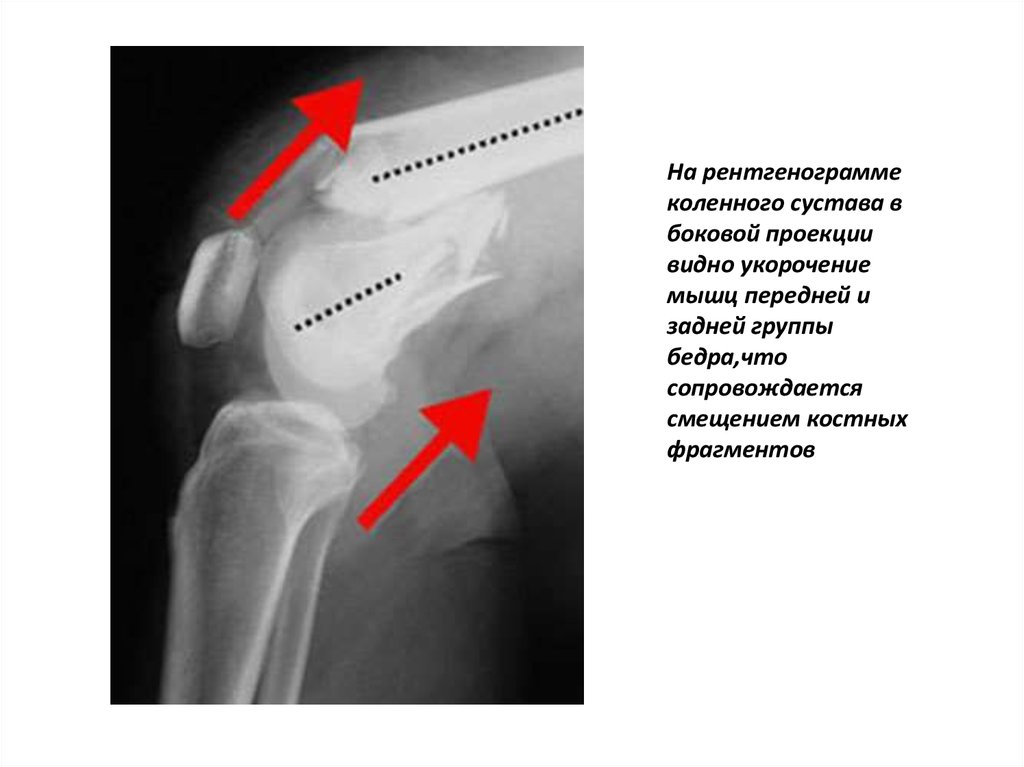

На рентгенограмме

коленного сустава в

боковой проекции

видно укорочение

мышц передней и

задней группы

бедра,что

сопровождается

смещением костных

фрагментов